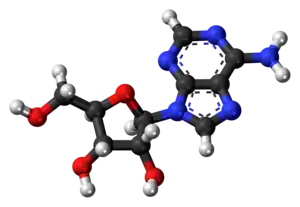

Adenosine consists of an adenine attached to a ribose via a β-N9-glycosidic bond.